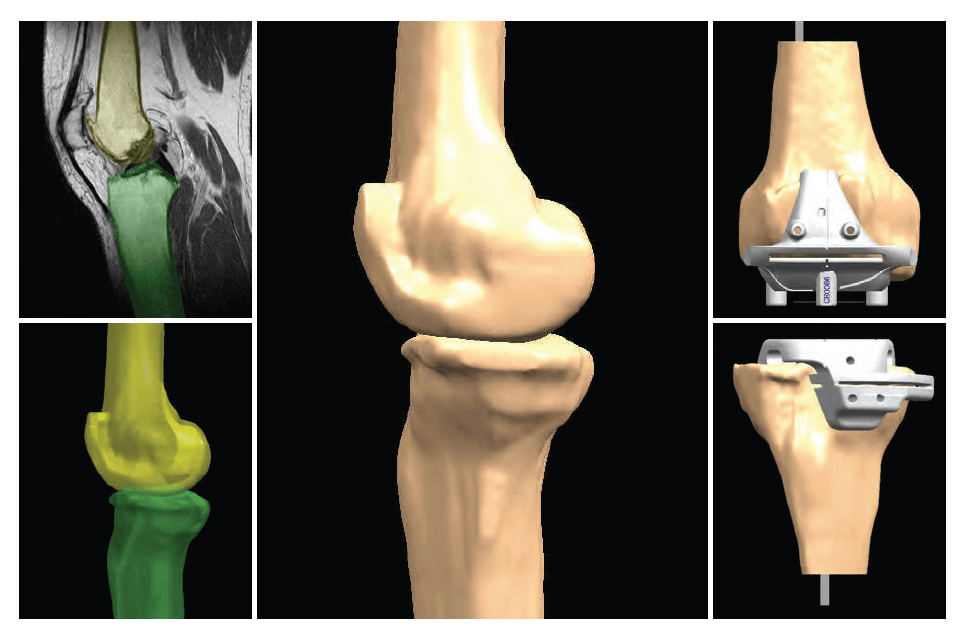

Εικόνα 5: Προεγχειρητικός σχεδιασμός χειρουργείου, υπολογισμός κλίσεων και στροφών με ακρίβεια χιλιοστού.

Εικόνα 6: Μαγνητική τομογραφία γόνατος, 3D μοντέλο και εξατομικευμένοι οδηγοί κοπής.

Η εξατομικευμένη αρθροπλαστική γόνατος PSI (Patient Specific Instrument, Zimmer – Biomet, USA) αποτελεί την αιχμή της συνεργασίας της ηλεκτρονικής τεχνολογίας και της ορθοπαιδικής χειρουργικής τεχνογνωσίας MIS (Minimal Invasive Surgery – Χειρουργική Ελάχιστης Επεμβατικότητας) προσφέροντας εξατομικευμένη αντίληψη της αρθροπλαστικής του γόνατος σε ασθενείς που πάσχουν από προχωρημένη εκφυλιστική, ρευματοειδή ή μετατραυματική αρθρίτιδα. Διαφοροποιείται σε σχέση με την κλασσική αρθροπλαστική στο ότι οι οδηγοί κοπής των αρθρικών επιφανειών μηρού και κνήμης και τοποθέτησης των εμφυτευμάτων κατασκευάζονται τρισδιάστατα, προσωποποιημένα για τον κάθε ασθενή, υπολογίζοντας με ακρίβεια χιλιοστού στις ανατομικές λεπτομέρειες του κάθε γόνατος και τις ιδιαιτερότητες στροφών και κλίσεων όλου του κάτω άκρου, από το ισχίο μέχρι την ποδοκνημική.

Για να επιτευχθεί αυτό απαιτείται η στενή συνεργασία μιας ομάδας ανθρώπων, ξεκινώντας από τον ειδικό ορθοπαιδικό που θα κάνει την ιατρική αξιολόγηση, τον ακτινολόγο που θα διενεργήσει μια μαγνητική ή αξονική τομογραφία ολόκληρου του κάτω άκρου, ώστε να γίνει η συνολική αξιολόγηση του κάτω άκρου ως ενιαία ανατομική και κινητική μονάδα και όχι ως μεμονωμένη άρθρωση μόνο, και του ειδικού κέντρου στο εξωτερικό, που θα σταλεί η εξέταση.

Κατόπιν θα δημιουργηθεί ένα μοντέλο τρισδιάστατης ηλεκτρονικής απεικόνισης του πάσχοντος γόνατος και θα αξιολογηθούν οι μηχανικοί και ανατομικοί άξονες ολόκληρου του σκέλους, γεγονός που θα προσδώσει ένα εξαιρετικό εμβιομηχανικό αποτέλεσμα μετά την χειρουργική επέμβαση.

Ο ειδικός ορθοπαιδικός θα μελετήσει το τρισδιάστατο μοντέλο της πάσχουσας άρθρωσης και θα την ανακατασκευάσει στον ηλεκτρονικό υπολογιστή, κάνοντας τις απαραίτητες διορθώσεις, σύμφωνα πάντα με το ανατομικό προφίλ του κάθε ασθενούς, το φύλο, τις παραμορφώσεις στους άξονες και στις συνδεσμικές τάσεις. Ειδική ομάδα επιστημόνων στις Βρυξέλλες, χρησιμοποιώντας τεχνολογία αιχμής, θα κατασκευάσει πρόπλασμα της άρθρωσης και τους ειδικούς οδηγούς τοποθέτησης των εμφυτευμάτων, που δεν μπορούν να χρησιμοποιηθούν σε άλλο ασθενή. Η διαδικασία διαρκεί περίπου 3 εβδομάδες, οι αποστειρωμένοι εξατομικευμένοι οδηγοί αποστέλλονται και προγραμματίζεται το χειρουργείο. Αλλά και τα τελικά εμφυτεύματα επιλέγονται μεταξύ πολύ μεγαλύτερης γκάμας μεγεθών και σχεδίων σε σχέση με την κλασσική αρθροπλαστική, προσεγγίζοντας το ιδεατό «ένα εμφύτευμα για κάθε ασθενή».